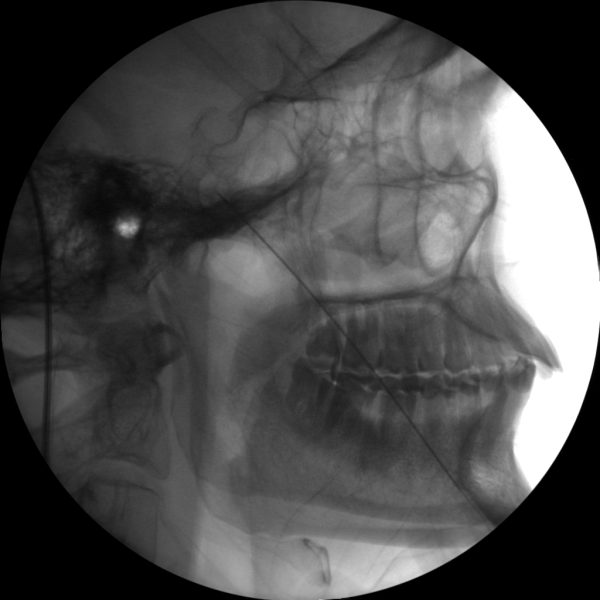

Nerve Blocks

Skan-C is an excellent choice for performing nerve blocks, a procedure that involves injecting anesthetic or anti-inflammatory medication near specific nerves to alleviate pain.